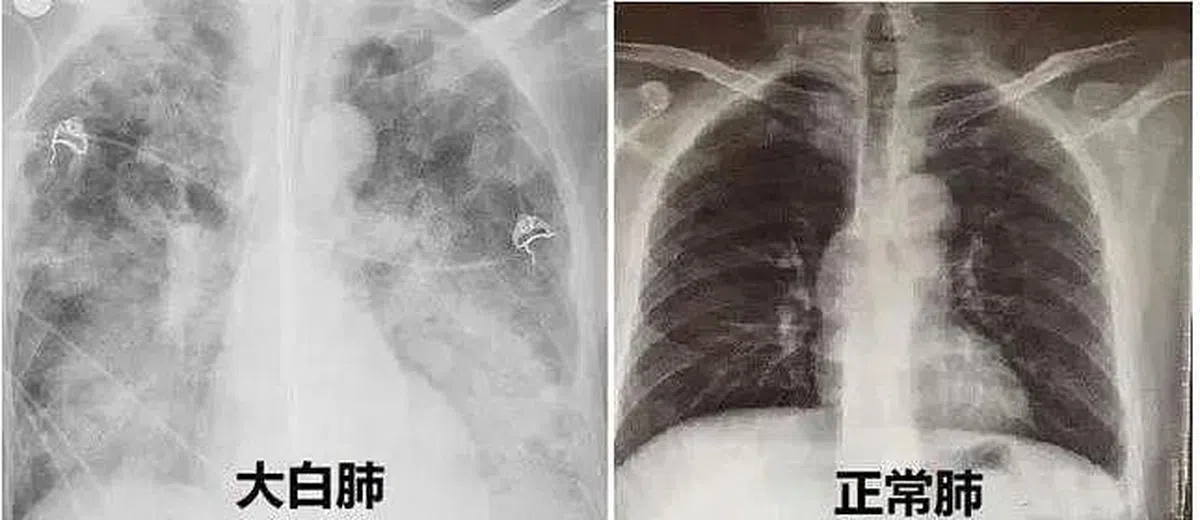

究竟什么是白肺?中国国家卫生健康委医政司司长焦雅辉星期二(27日)说,白肺是肺部影像学表现的一个口语化描述。一般来讲,肺部炎症比较重、渗出比较多,即白色影像区域面积达到70%到80%之时,在临床上被口语化称为白肺。

焦雅辉进一步解释,之所以会出现“白肺”,首先与肺部影像学的呈像原理有关。她说,肺部是由肺泡组成的,肺泡里面充满空气,进行CT或者X线检查的时候,射线穿过肺泡,影像表现是黑色区域;但是,当肺泡里出现炎症或感染,有渗出液和炎性细胞的时候,肺泡就被这些渗出液和炎性细胞所填充,射线就穿不透,在影像学上出现白色区域。白色区域反映出来的是渗出物的影像学表现,并不是肺脏组织实体变成了白色。

焦雅辉强调,并不是说只要肺部出现了炎症就都是白肺,白肺是比较严重的肺炎表现,这个阶段患者会出现低氧血症或呼吸窘迫。随着渗出液的吸收、炎症的消退,白肺的表现也会逐渐消退,肺部的影像学表现会逐步恢复为黑色区域。